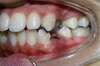

L'appareillage